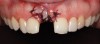

To place an implant without inducing recession, papillae-sparing incisions were created on the mesial and distal of the edentate area at site No. 8. Vertical incisions were made 1 mm away from adjacent teeth and connected with a mid-crestal incision (Figure 13). The extent of the vertical incisions was 3 mm buccally and lingually to expose the alveolar ridge. Horizontal and vertical bone regeneration was clinically confirmed (Figure 14). A 3.3-mm x 12-mm bone level tapered, narrow-connection implant (Straumann, straumann.com) was inserted, and it attained initial primary stability at 25 Ncm (Figure 15 and Figure 16). It was desired to have more than 1 mm of bone buccal and lingual to the implant so as to avoid bone resorption and recession. Then, 4-0 Vicryl single interrupted sutures were used to close the flap (Figure 17).

Fig 13. Papillae-sparing incisions connected mid-crestally.

Figure 13

Fig 14. Clinical confirmation of a 6.4-mm wide ridge.

Figure 14